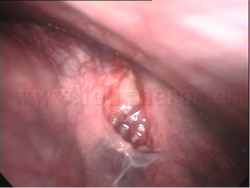

Biopsia de tumores de mediastino

Linfoma de mediastino anterior